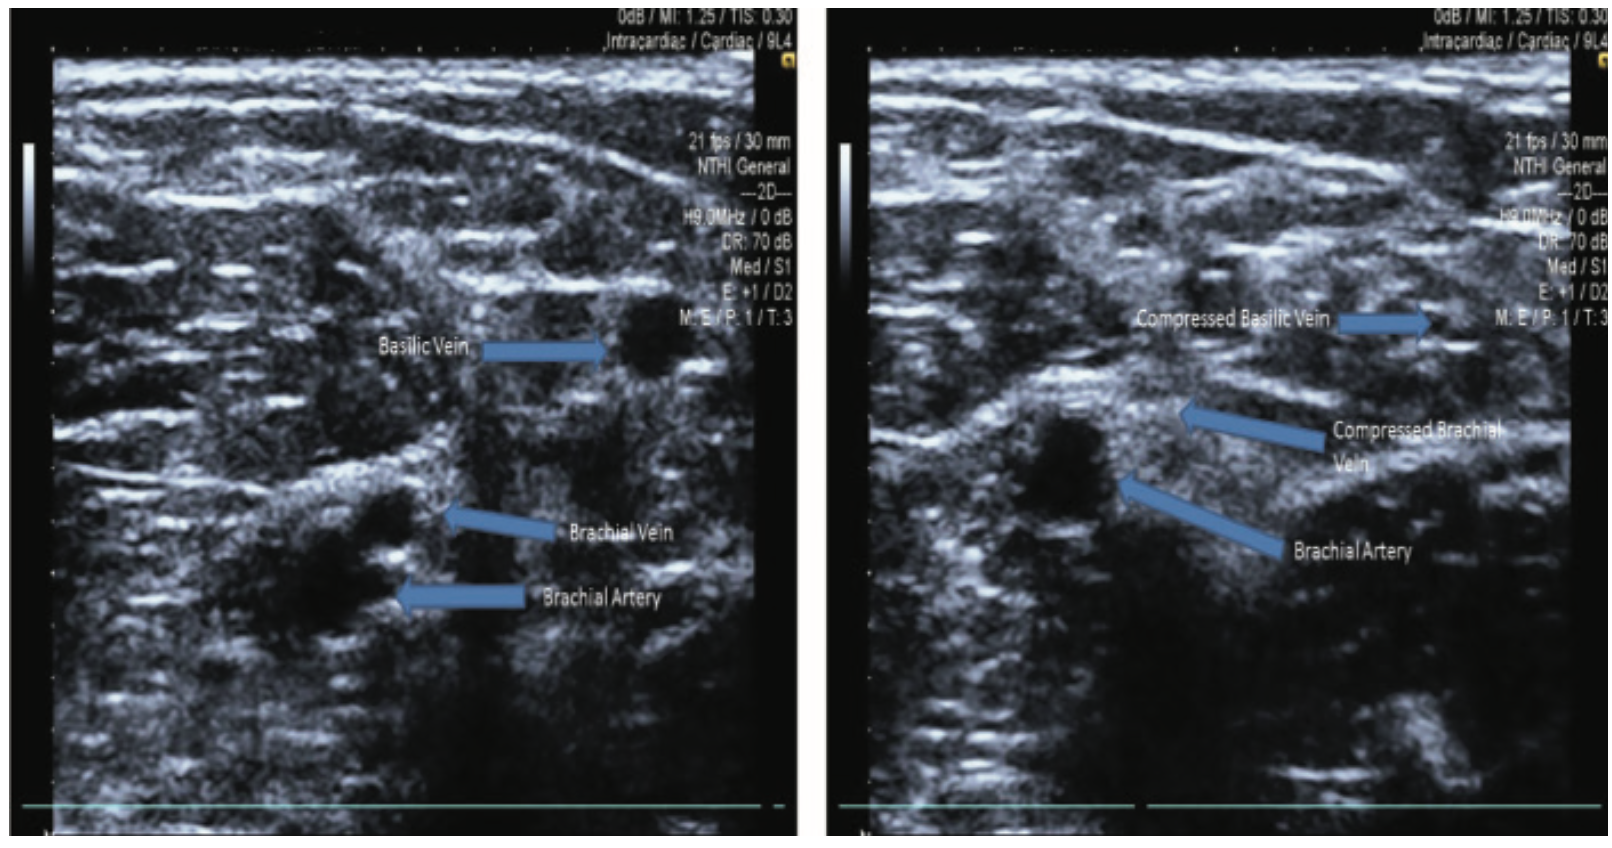

The brachial artery, vein, and nerve all lie in close proximity to each other. Therefore, US offers the ability to visualize and access the correct vessel during brachial access. Brachial artery access is associated with higher vascular complication rates than radial or femoral artery access, and compressive complications and nerve impacts can occur because of brachial artery or vein punctures.6 Brachial artery and vein access can be optimized by using micropuncture needles and US guidance; this technique allows the operator to effectively visualize vessels, minimize access trauma, and avoid nearby nerves and vessels.6 Brachial artery access is not commonly performed in coronary angiography and is generally performed on people with advanced atherosclerotic disease. Therefore, US guidance provides the advantage of minimizing additional vascular issues associated with brachial artery access (Figure 6).

US insertion has been determined to be fast and reliable for use in upper arm venous access. It allows operators to isolate the cephalic, brachial and basilic veins. As radial artery access increases for coronary angiography, upper arm vein access is becoming more commonly used for right heart catheterization. Each of the three upper arm veins can be accessed, but they should be evaluated to determine size, location and course to choose the best access route. The cephalic vein may be small-caliber and tortuous, and the brachial vein is in close proximity to the brachial artery and nerve. In many cases, the basilic vein is large, has a straighter course to the heart, and avoids arterial and nervous system anatomy. Therefore, ultrasound not only isolates the veins, but also allows access into a vessel that is large enough to accommodate swan catheters, and more easily travel to the heart and pulmonary arteries. The antecubital fossa houses the deep brachial vein, which is often posterior to the median nerve or the brachial artery. The basilic vein is more isolated and is frequently the safest choice in ultrasound-guided peripheral venous access.7